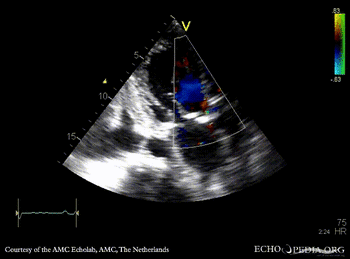

PLAX: Color Doppler, mild aortic regurgitation